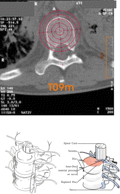

Wirbelsäulenimplantat und Tools für die

Wirbelfusion als hochpräzise minimalinvasive chirurgische

Tools

Führungsinstrumente für Diamantwerkzeugen

im chirurgischen OP für den minimalinvasiven Einsatz